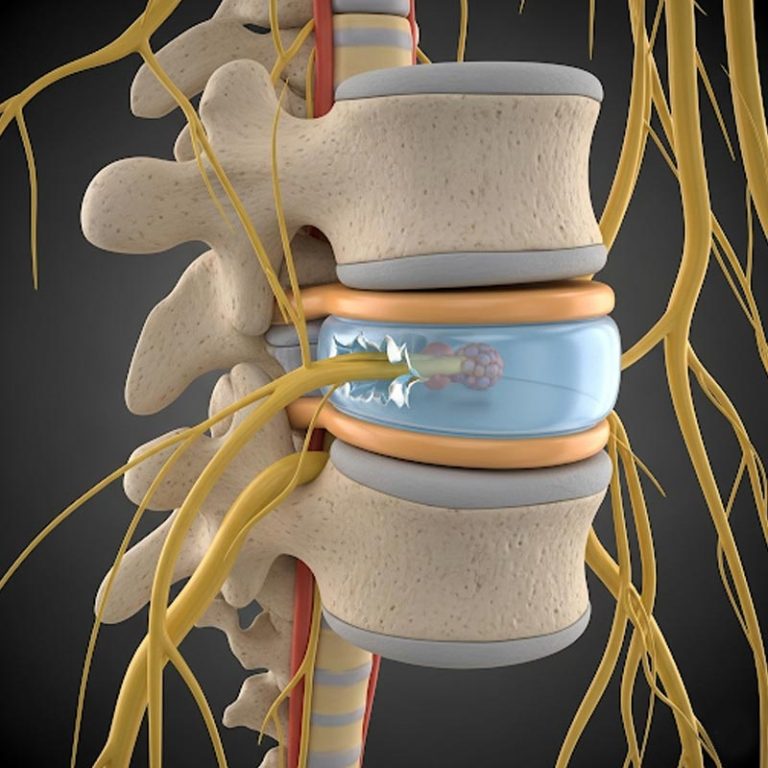

A disc bulge occurs when the soft inner portion of a spinal disc pushes outward, causing the disc to...

A slipped disc, also called a herniated disc, occurs when the soft inner gel of a spinal disc pushes...

Degenerative Disc Disease (DDD) is a condition where the spinal discs, which act as cushions between...